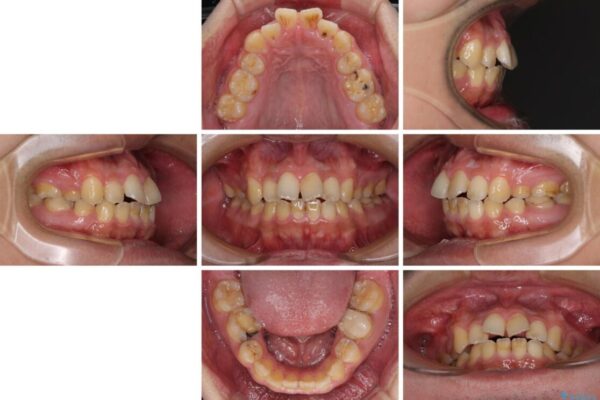

治療前

• 後戻りでデコボコの前歯 インビザライン矯正治療 治療前画像